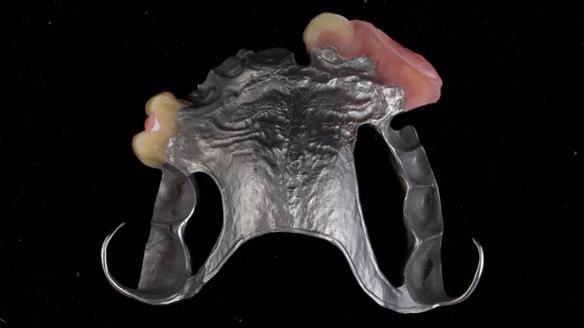

Welcome to Newsletter 67, where I will detail the making and fitting of an upper metal-based partial denture/splint (“Combat denture”) for Brian, a patient with a powerful locked occlusion and deep overbite. The full protocol workflow is presented here.

- Bruxism: The upper and lower teeth are worn and chipped due to heavy clenching and grinding. With a powerful bite and limited space for replacement teeth, dental implants supported fixed teeth are not recommended. A simpler solution is a metal-based partial denture/splint (“Combat denture”) as planned below. This will act as a splint to protect and replace the missing teeth.

- Restored Teeth: The remaining upper teeth and lower back teeth have large fillings and crowns, making them structurally weak. The new denture will reduce the forces on these teeth to help them last longer, though they may still require new restorations or extractions occasionally.

Treatment Process: I provided the clinical work, while Rowan Garstang handled the technical work. The treatment required five visits to fit the RPD. The worn lower anterior teeth were then built up. Unfortunately, I did not check the guidance on the denture teeth after this, and tooth 11 fractured off the denture. Brian was very understanding, and I adjusted the denture thoroughly. It has been fracture-resistant and trouble-free for the last three years.